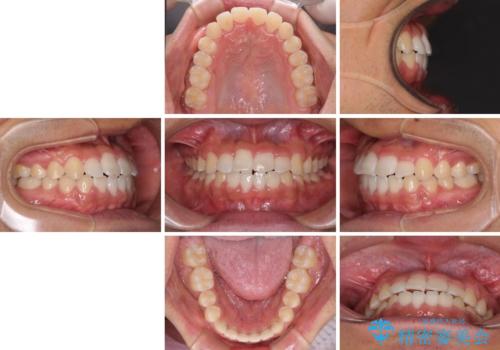

今後はすり減ってしまった歯の形をセラミッククラウンで改善したいとのことで、クロスバイトが改善し咬みやすくなった時点で装置を外すこととしました。

1年で治療を終えることができ、患者様には大変満足していただきました。